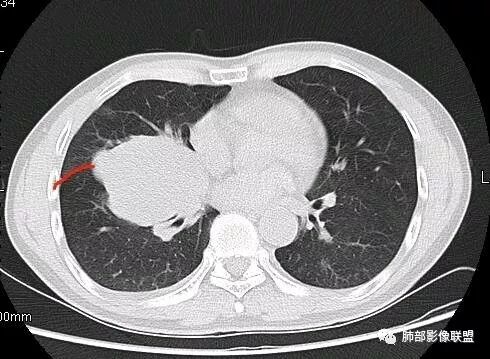

南边:深分叶、大肿块

南边:主体在下叶前基底段

南边:边缘膨隆

南边:中叶、下叶背段支气管推移

南边:中叶支气管腔内似有粘液栓,外侧段有炎性病变

南边:有老师问为啥考虑中叶支气管受压?不是支气管来源的?

1、主体病灶在下叶

2、支气管腔还在,有移位